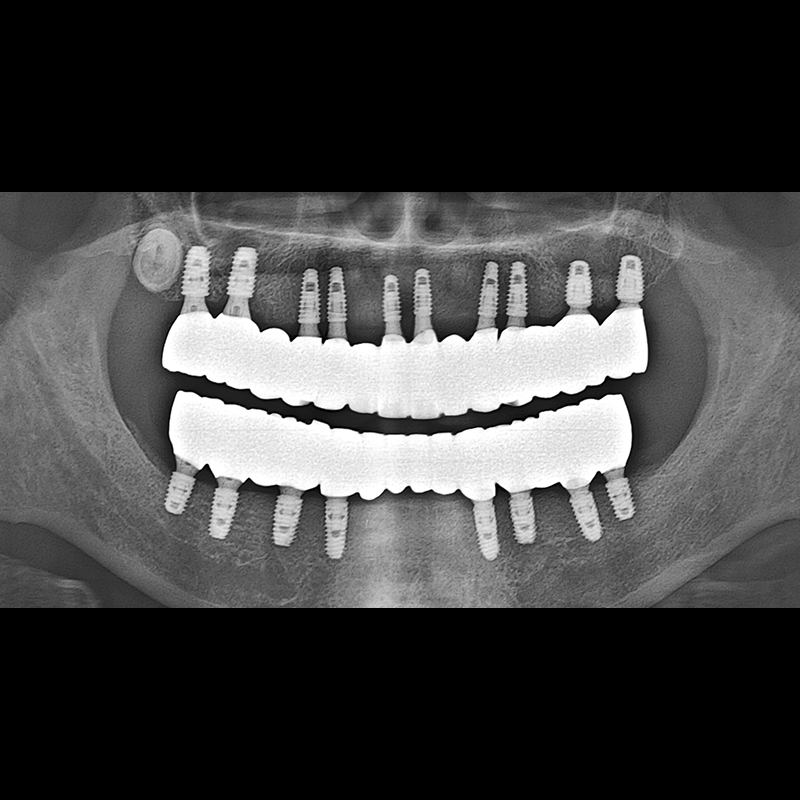

BEFORE AFTER

种植牙前后的照片 2025.05.30

在缺失的牙齿部分和难以挽救的牙齿位置植入了种植牙。